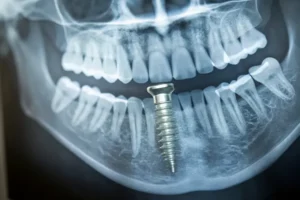

تعد زراعة الأسنان الفورية، المعروفة أيضًا باسم زراعة اليوم الواحد، هي أحدث التقنيات في طب الأسنان، حيث تُزرع الغرسة مباشرةً في عظم الفك بعد خلع السن أو فقدانه، دون الحاجة إلى الانتظار لفترة شفاء طويلة كما في الزراعة التقليدية.

يتيح هذا الإجراء في كثير من الحالات تركيب تاج مؤقت في نفس اليوم، مما يساعد المريض على استعادة مظهر ووظيفة السن بسرعة وفعالية.

- تركيب الغرسة فورًا

يضع الطبيب غرسة من التيتانيوم في تجويف السن المخلوع، لتكون بمثابة جذر السن الجديد.